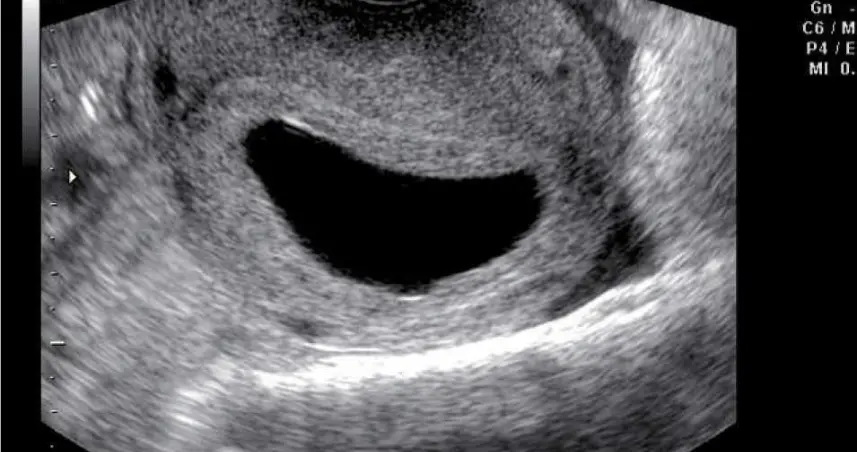

SANTO DOMINGO.- Llegar a las seis semanas de embarazo significa que ya los latidos del bebé pueden verse a través de un eco intravaginal, según la doctora Lilliam Fondeur.

Sin embargo, pueden darse casos en que la mujer puede tener un saco anembrionado, lo que significa que no hay un embrión dentro del mismo.

Fondeur explica que si entre las semanas 7 a 8 si no se figura un embrión es porque no hay embarazo.